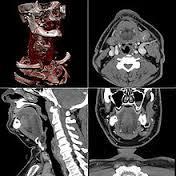

接下来就是磁共振,磁共振的远离简单的说:正常情况下人体内的氢原子核处于无规律的进动状态,当人体进入强大均匀的磁体空间内,在外加静磁场作用下原来杂乱无章的氢原子核一齐按外磁场方向排列并继续进动,当立即停止外加磁场磁力后,人体内的氢原子将在相同组织相同时间下回到原状态;这称为驰豫,而病理状态下的人体组织驰豫时间不同,通过计算机系统采集这些信号经数字重建技术转换成图像就可以给临床和研究提供科学的诊断结果。

磁共振和CT的区别主要在于成像的性质,CT是根据组织的密度,由于人体不同组织的密度不同,来发现病灶;而磁共振是判断不同加权所产生的不同信号。磁共振于对软组织滑膜、血管、神经、肌肉、肌腱、韧带、和透明软骨的分辨率高。由于其特殊的性质,磁共振看骨头不行,而在大脑的检查中则有着不可替代的作用。

之前提到医学影像学的发展与其说是医学的发展,不如说是工业技术的发展,计算机三维重建技术就是一个很好的例子。过去医生看病人的CT片,都是一张一张来看的,而当下扫一个病人的图像,就有1000幅图像,一天下来会产生万幅图像,医生根本没法彻底看完这些片子。借助医学影像学,可以先对这些片子进行后处理,使之融合成为一个三维立体,这样医生就可以先看到直观的立体图像,正常组织和病灶之间的结构也一目了然。